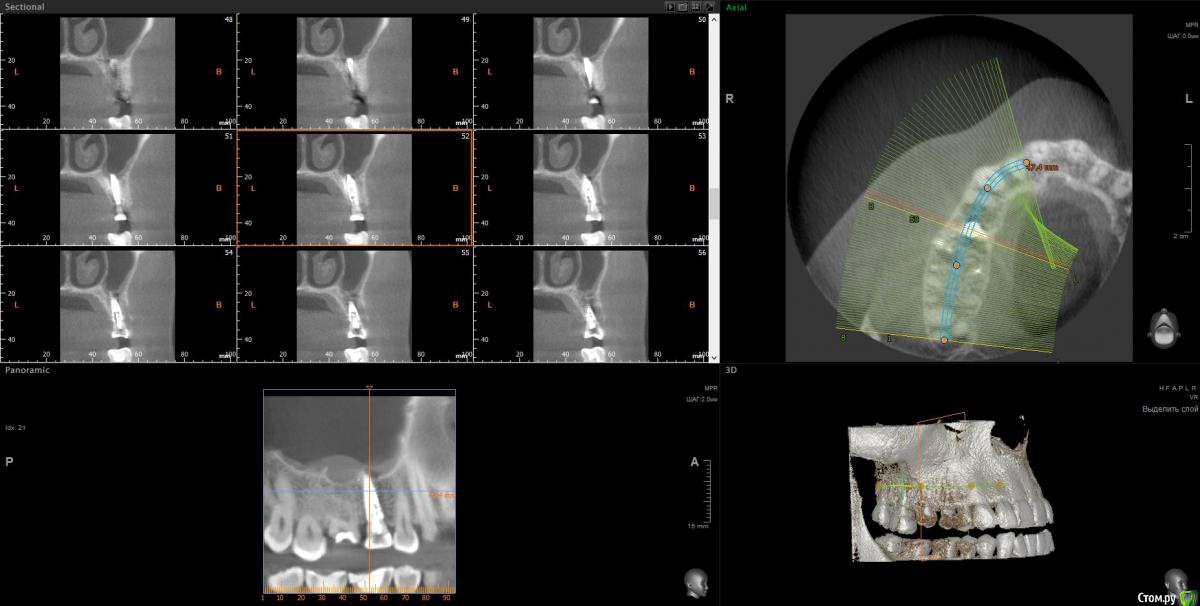

anvladd Опубликовано 31 января, 2017 Поделиться Опубликовано 31 января, 2017 (изменено) Как с носом, не гайморит ли ? 3 d бы глянуть, хотя бы этот сегмент. Изменено 31 января, 2017 пользователем anvladd Ссылка на комментарий

Весна2009 Опубликовано 31 января, 2017 Автор Поделиться Опубликовано 31 января, 2017 КТhttps://yadi.sk/d/ETucH2JNzeF9X Ссылка на комментарий

wladdX Опубликовано 2 февраля, 2017 Поделиться Опубликовано 2 февраля, 2017 Несколько скриншотов на скорую руку. Ссылка на комментарий